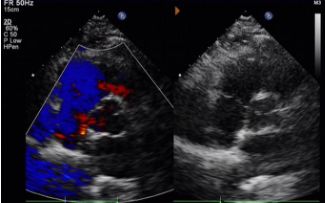

Today, we share a remarkable case highlighting 1-year post-op outcomes of MemoSorb in treating a complex long-tunnel PFO (12mm length, 1.4mm width), with a focus on serial echocardiographic evidence of device degradation and clinical symptom resolution.

Da 1 a 9 mesi da giorno:

Nessuno shunt residuo osservato.

Riduzione graduale dell'ecogenicità del dispositivo.